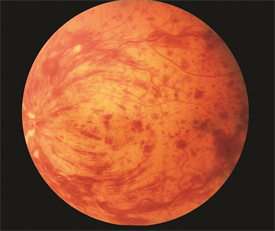

3. Central retinal vein occlusion: often times sudden but occasional gradual (days-weeks) vision loss due to swelling of the macula. Risk factors: same as above and glaucoma. Think of this as a DVT for the eye. PE: decreased visual acuity. "Blood and thunder" on fundoscopy. ED role: Evaluate for cause or presence of other pathologies secondary to a hypercoagulable state (DVT, PE, sickle cell, etc.). Refer to optho and will need PCP to address concurrent risk factors.